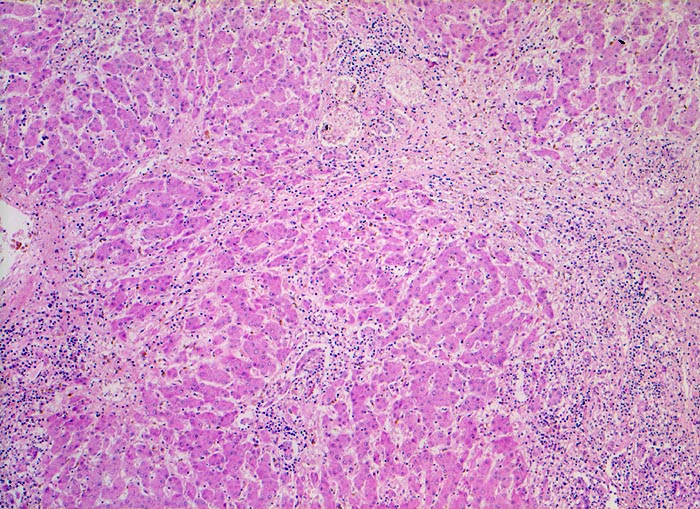

Das histologische Bild der akuten Hepatitis vom Virustyp ist gekennzeichnet durch eine lobuläre Entzündung bei fehlender portaler Fibrose und nur geringer entzündlicher Infiltration der Portalfelder. Es finden sich ballonierte Hepatozyten, Apoptosen (> 1164) und fleckige Nekrosen. Perivenuläre Nekrosen, Brückennekrosen oder konfluierende multilobuläre Nekrosen und eine läppchenzentrale Cholestase können vor allem in klinisch fulminant verlaufenden Fällen nachgewiesen werden. Zahlreiche Makrophagen, welche Diastase-PAS positives Zeroidpigment (> 4319) von phagozytierten nekrotischen Hepatozyten enthalten, zeugen im subakuten Stadium von einer abgelaufenen akuten Hepatitis mit Parenchymnekrosen. Eine Unterscheidung der verschiedenen Typen der viralen Hepatitis und einiger Formen medikamentöser Hepatitiden gelingt rein morphologisch aufgrund des unspezifischen Bildes meist nicht. Für eine ätiologische Klassifizierung sind zusätzliche klinische Angaben erforderlich (Anamnese, Medikamente, Serologie).

• Regelrechte Läppchenarchitektur.

• Lobuläre gemischte Entzündung.

• Portale gemischte Entzündung.

• Fehlende Fibrose.